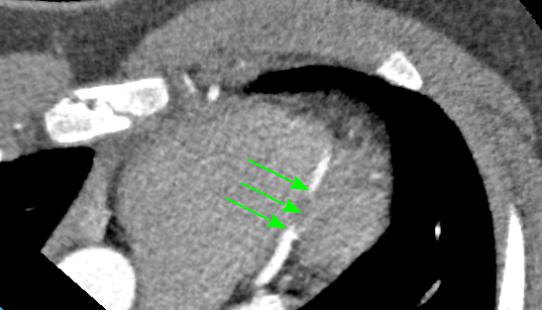

На рисунке показаны серии компьютерной томографии сердца пациента с миокардиальным мостиком передней межжелудочковой артерией (до операции). Стрелками обозначен наиболее глубоко проходящий сегмент артерии. |